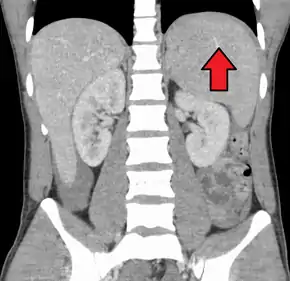

Splenomegaly due to mononucleosis resulting in a subcapsular hematoma

Spleen enlargement is common in the second and third weeks, although this may not be apparent on physical examination. Rarely the spleen may rupture.[24] There may also be some enlargement of the liver.[22] Jaundice occurs only occasionally.[14][25]

Splenomegaly is a common symptom of infectious mononucleosis and health care providers may consider using abdominal ultrasonography to get insight into the enlargement of a person's spleen.[58] However, because spleen size varies greatly, ultrasonography is not a valid technique for assessing spleen enlargement and should not be used in typical circumstances or to make routine decisions about fitness for playing sports.[58]